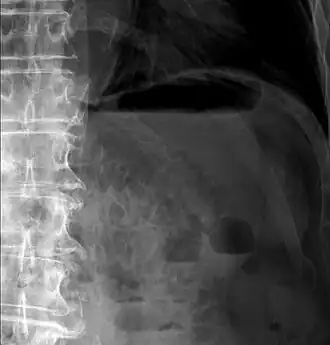

Pneumatosis intestinalis in computed tomography with intestinal ischemia. Lung window for better representation of the gas deposits in the intestinal walls. - Upright AP radiograph showing gas in the wall of the small bowel in the left upper quadrant indicative of pneumatosis intestinalis.

- Coronal reformatted MDCT image showing extensive pneumatosis intestinalis in the left upper quadrant small bowel. The pneumatosis is more cystic and nodular in the small bowel in the midline and the right of midline. This patient had a relatively benign presentation without bowel ischemia and was treated conservatively.